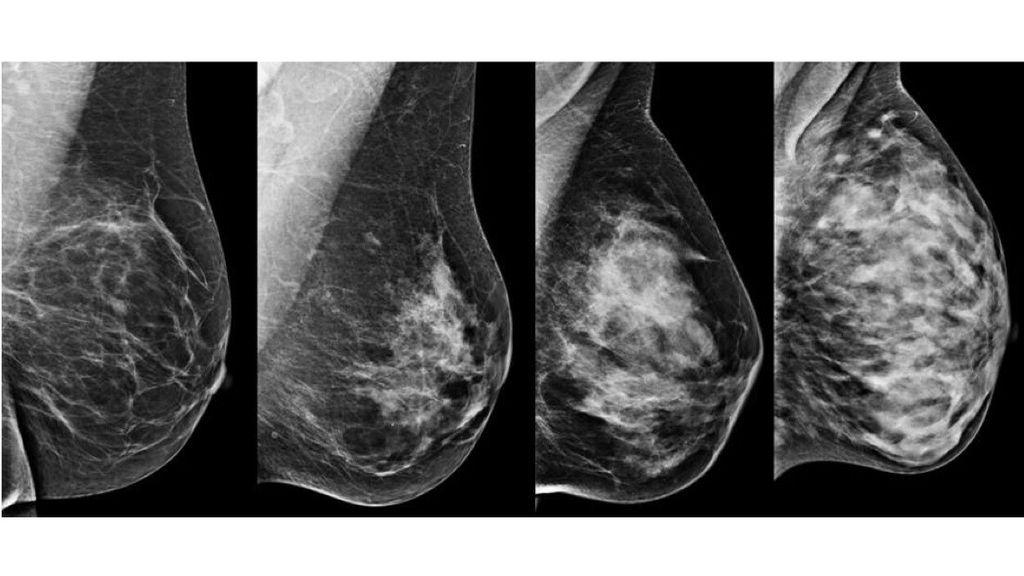

Het UMC Utrecht is een nieuw onderzoek begonnen om borstkanker eerder op te sporen bij vrouwen met dicht borstklierweefsel. Deze vrouwen hebben een veel grotere kans op borstkanker, terwijl juist bij hen tumoren slecht zichtbaar zijn op de mammografie tijdens het bevolkingsonderzoek.